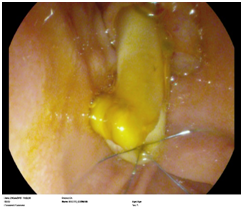

Figure 2 Fungal infection forming a “fungal ball”.

Fungal infections (Figure 2)